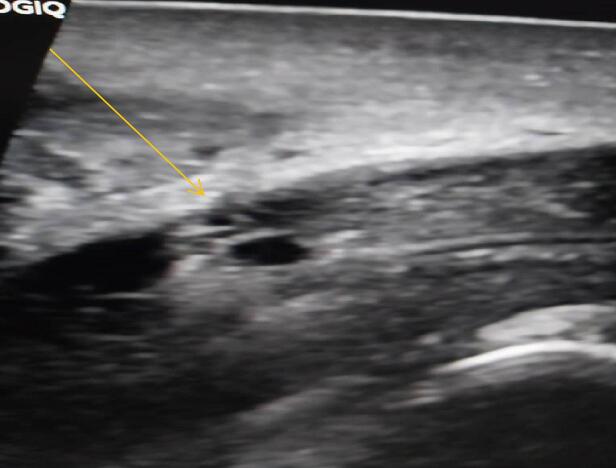

We report a case of a 27-year-old male who was referred to our facility from a secondary care hospital, he presented to the emergency department 34 h after sustaining injury to the penis during sexual intercourse with his wife. During intercourse he felt an abrupt pop sensation in the penis which was painful initially but the pain subsided immediately afterwards, it was associated with detumescence and gradual swelling of the penis and scrotum. He was voiding normally and there was no blood in urine. The review of systems was normal and the past medical history was uneventful. On examination the penis was swollen particularly in the proximal part, it was deviated to the left side, non-tender, the rolling sign was present on the right side of the penile shaft (Fig. 1). A penile ultrasound was performed which revealed a tear in the left proximal lateral corpus carvenosus with a subcutaneous hematoma (Fig. 2).

Fig. 2.

Tear in the left proximal lateral corpus carvenosus with hematoma.(yellow arrow).